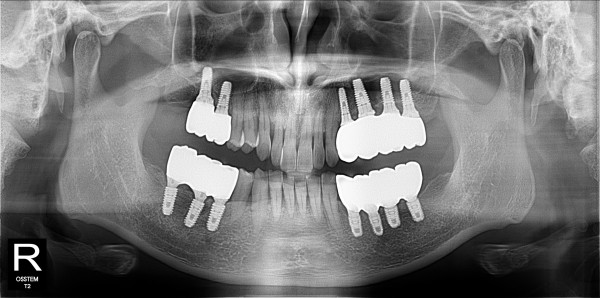

구치부 임플란트 최고관리자 0건 23-11-07 18:29 본문 구치부 임플란트 목록 이전글구치부 임플란트 23.11.07 다음글구치부 임플란트 23.11.07 댓글목록 0 댓글목록 등록된 댓글이 없습니다.